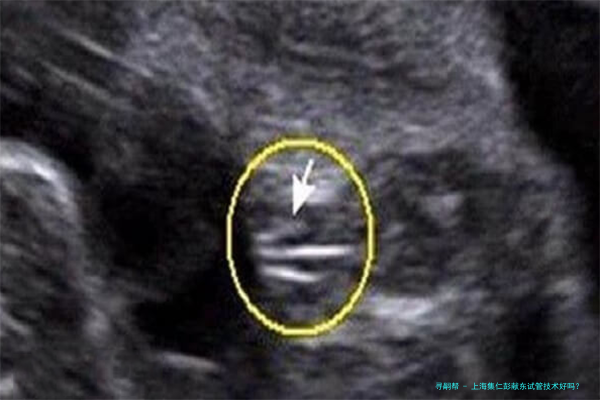

试管婴儿技术是一种人类辅助生殖技术,主要适合于因各种缘故导致的试管婴儿助孕夫妇。这个技术通过将卵子和精子在体外受精后,培育成初期胚胎,又将胚胎移植到本人体内内不断发育,一直到分娩。上海集仁遗传与不育诊疗中心的试管婴儿技术涵盖了多个方向,囊括但不仅限于:

PGD/PGS(胚胎植入前基因诊断/筛选):运用于筛选出正常的胚胎进行移植,降低遗传性疾病传达的风险。